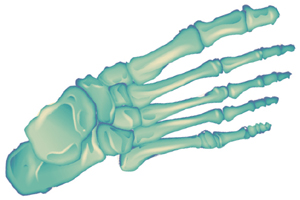

They consist of two limbs that total 62 bones between them. They are formed by the pelvic waist (pelvis), the femur or thigh bone and the bones of the legs and feet.

The pelvis is made up by the coxal bones, the sacrum and coccyx. The femur (thigh bone) is the longest bone of the human body. The bones of the leg (tibia and fibula) are born at the knee and go all the way down to the ankle.